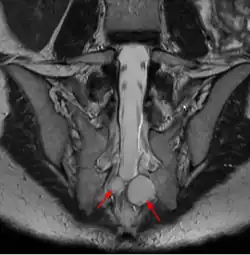

Eine Tarlov-Zyste (auch perineurale Zyste, Wurzeltaschenzyste) ist eine liquorgefüllte Aussackung der Nervenwurzel der Spinalganglien. Diese sind meningeale Zysten vom Typ II. Sie sind extradural gelegen, aber gerade am Ausgang aus dem Spinalkanal im Bereich der Foramina intervertebralia. Sie treten ausschließlich an den hinteren Nervenwurzeln auf, da nur die Zellkörper der sensorischen Nervenzellen der Hinterhornganglien aus dem Rückenmark ausgewandert sind und dabei eine Aussackung des Liquorraums bilden. Durch überhöhten Liquordruck kann sich Flüssigkeit in diesen Räumen sammeln, und da der Rückfluss wie bei einem Überdruckventil nicht möglich ist, können sie zu Zysten anschwellen. Der Druck ist im Bereich des Kreuzbeins am höchsten, dort finden sich Tarlov-Zysten am häufigsten. Frauen sind wesentlich häufiger betroffen.[1]

Oft treten einzelne Zysten auf, aber es können auch zahlreiche Tarlov-Zysten entstehen, dann oft auch auf Höhe der Brustwirbelsäule. Zur Diagnostik dient neben der Magnetresonanztomographie auch eine CT-Myelographie. Bei zahlreichen Zysten kann die Ursache in einer genetischen Bindegewebserkrankung liegen. Eine Assoziation mit Tarlov-Zysten wurde beim Marfan-Syndrom, beim Ehlers-Danlos-Syndrom und beim Loeys-Dietz-Syndrom beschrieben. Insbesondere beim Marfan-Syndrom finden sich oft weitere sakrale Veränderungen, vor allem eine sakrale Ektasie.

Tarlov-Zysten sind meist asymptomatisch, und in der Regel Zufallsbefunde. In MRT-Aufnahmen der Lendenwirbelsäule fanden sich Tarlov-Zysten bei 1,5 – 2,1 % der Patienten. Sie können aber bei entsprechender Größe lokale Druckeffekte hervorrufen.[3] Nur selten sind Tarlov-Zysten durch Druck auf benachbarte Nervenwurzeln ursächlich für Rückenbeschwerden, und dann meist in Form eines Nervenkompressionssyndroms, z. B. als Ischialgie. Aber auch lokale Schmerzen mit einer diffusen schwer lokalisierbaren Lumbalgie, oder Beschwerden an der Brustwirbelsäule, Blaseninkontinenz und Stuhlinkontinenz können selten auftreten. Bei sakralen Tarlov-Zysten kann das Aktionspotential des Nervus suralis in der Elektroneurographie verändert sein[4], was als Hinweis dienen kann, dass die Zyste tatsächlich klinisch bedeutend ist.